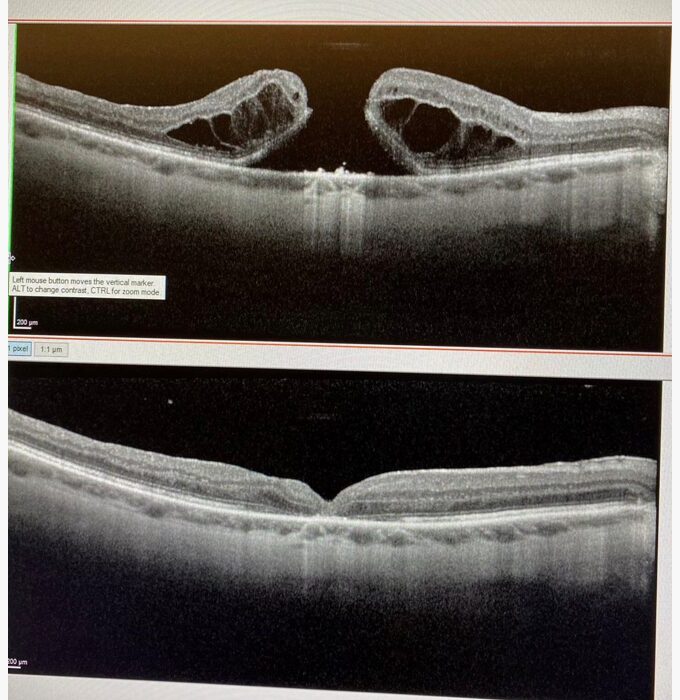

PD Dr. med. J. Guber ist ein führender Spezialist im Bereich Netzhauterkrankungen und Netzhautchirurgie. Am international besetzten Retina Symposium (Oftacafe 2023) in Lugano spricht er über die Behandlung von Makulalöcher mittels ILM-Flap. Eine spezielle Methode, die u.a. durch Dr. Guber entwickelt wurde.